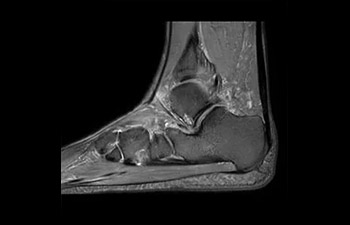

En una sociedad en la que los reembolsos son cada vez menos cuantiosos y las enfermedades crónicas se traducen en un aumento de los procedimientos de RM y en tiempos de espera más largos, los servicios de radiología se ven sometidos a una presión cada vez mayor. La aceleración pone en riesgo la calidad de la imagen o bien se puede aplicar a todo el espectro de las exploraciones rutinarias. Por lo tanto, para satisfacer la creciente demanda de productividad, todavía es necesario dar un paso adelante más en cuanto a la aceleración. Aprovechando nuestra dilatada posición de liderazgo en el ámbito de la velocidad (de la mano de SENSE), Philips presenta Compressed SENSE, un avance en términos de productividad.

• Es una innovadora técnica de aceleración que no solo permite agilizar las secuencias, sino todo el estudio. • Implementación especial con la que las exploraciones en 2D y 3D pueden llegar a ser hasta un 50% más rápidas con una calidad de imagen prácticamente equivalente.1

• Se puede usar con todos los contrastes y con todas las regiones anatomías.